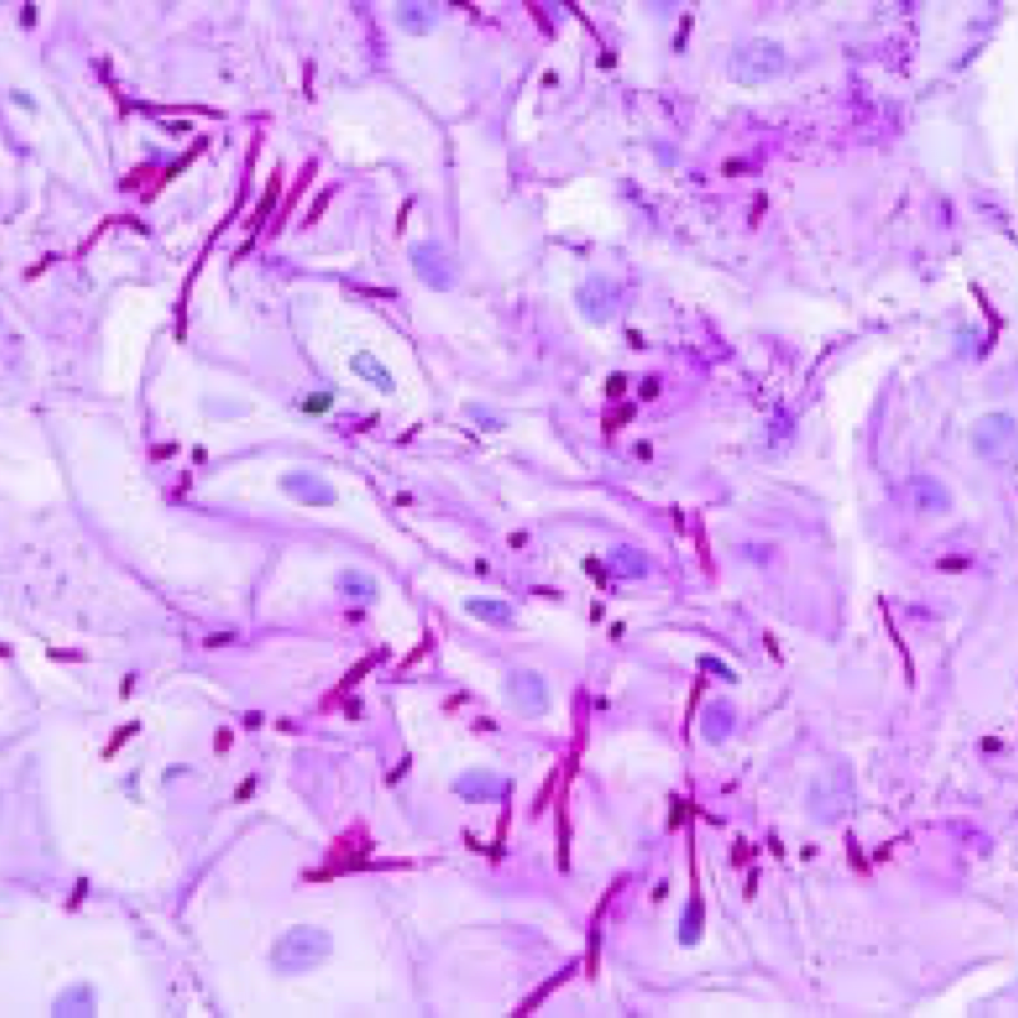

Candidiasis

Las candidiasis constituyen un grupo de infecciones causada por un hongo oportunista que puede tener expresión cutánea, gastrointestinal, sistema respiratorio y genitales, de los cuales Cándida Albicans es la más frecuente.

Estos hongos están siempre presentes en piel, mucosa del tracto digestivo, sistema genitourinario y respiratorio de la mayoría de las personas, pero se encuentran controlados por otros microrganismos no patógenos.